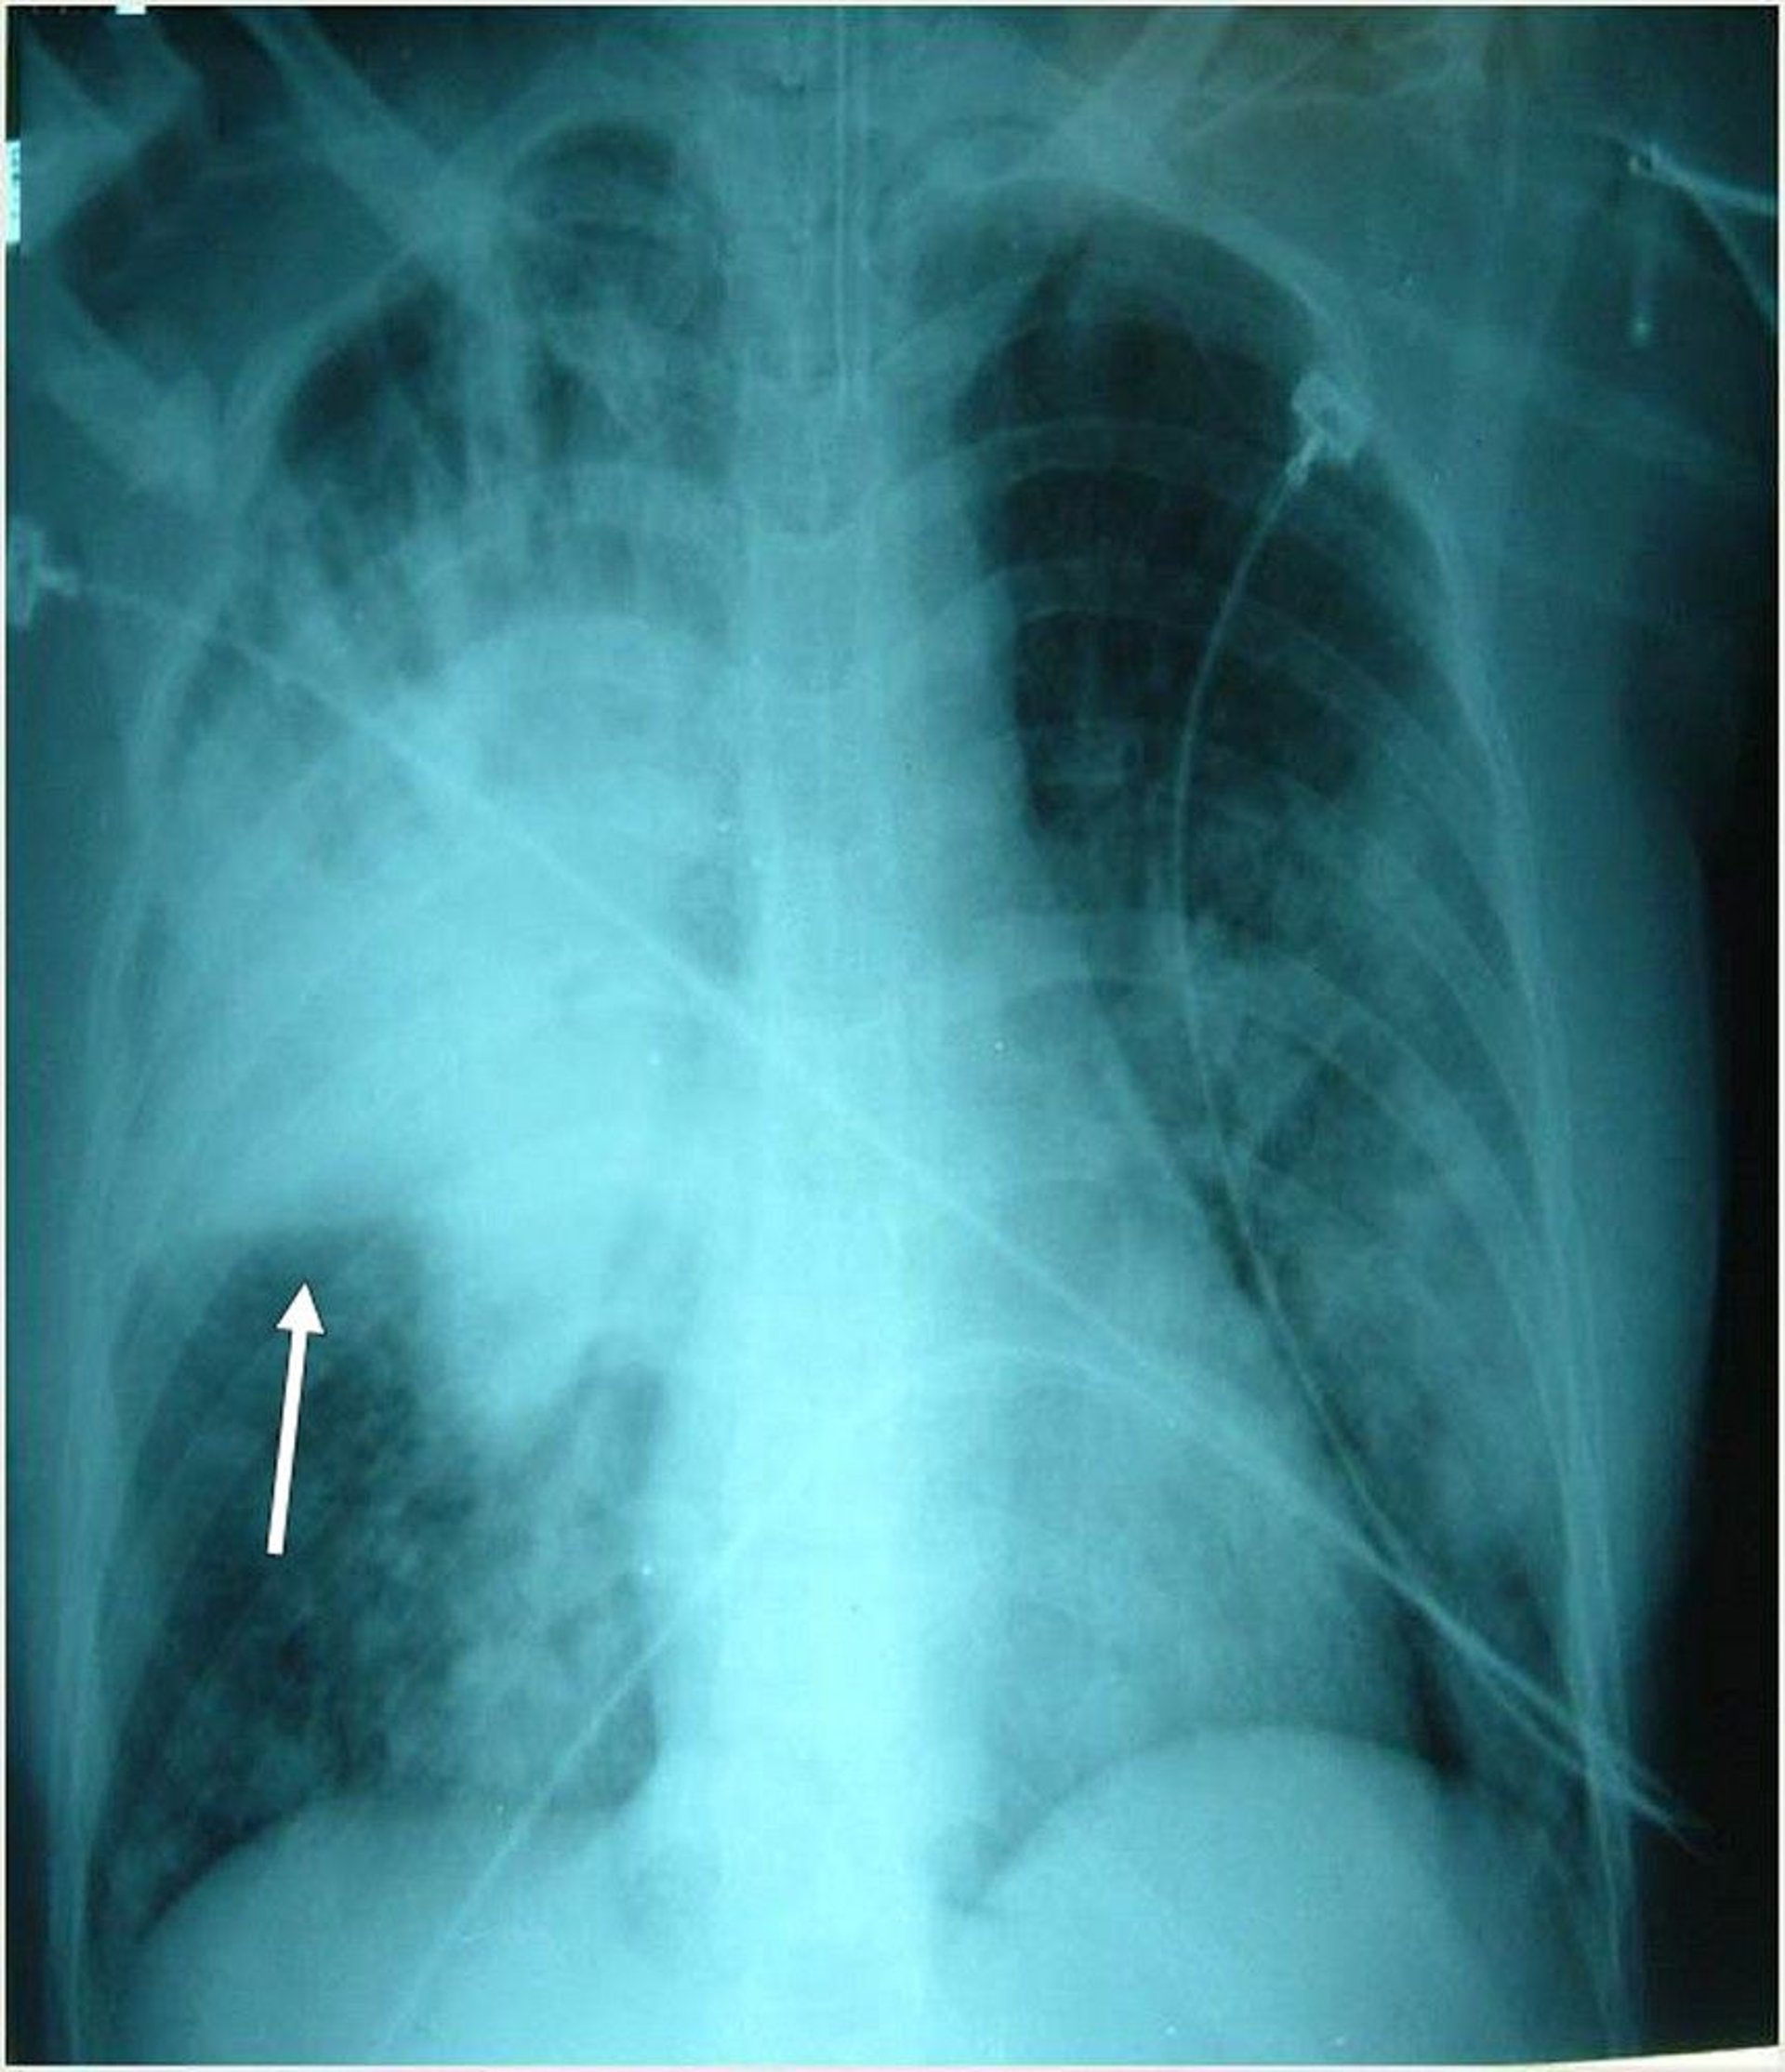

This intubated patient has multiple bilateral infiltrates, most prominently in the right upper lobe. Arrow indicates the right horizontal fissure.

Photo courtesy of Thomas M. File, Jr., MD MSc MACP FIDSA FCCP.